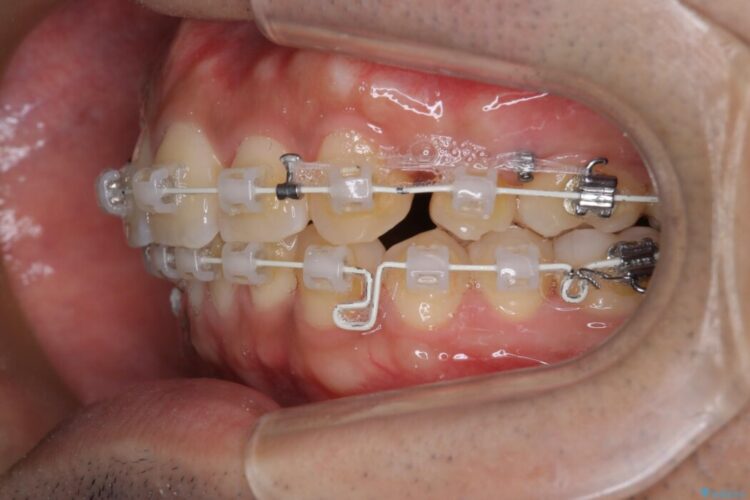

重度の叢生を審美ワイヤー装置で整える

歯列のガタガタさをなおしたいとのことで来院されました。

比較的重度の叢生であり整えるためのスペースが足りなかったため抜歯を行うことで確保し、ワイヤー装置にて配列を行いました。

当初はインビザラインでの治療をしていましたが、装着時間の確保が出来ないことからワイヤー矯正治療へ移行しています。

特に奥歯の捻転がひどく、整った歯列となるまでに時間は要しましたが、きれいな仕上がりに患者様には大変ご満足いただけました。